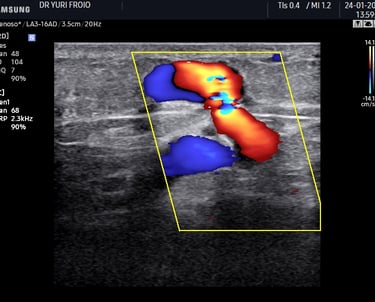

Ecografia Vascular com Doppler

A ecografia vascular com Doppler avalia o fluxo sanguíneo em artérias e veias identificando obstruções, varizes e tromboses. É um exame não invasivo, essencial para diagnóstico e acompanhamento de doenças vasculares. Proporciona informações detalhadas para uma abordagem clínica precisa.